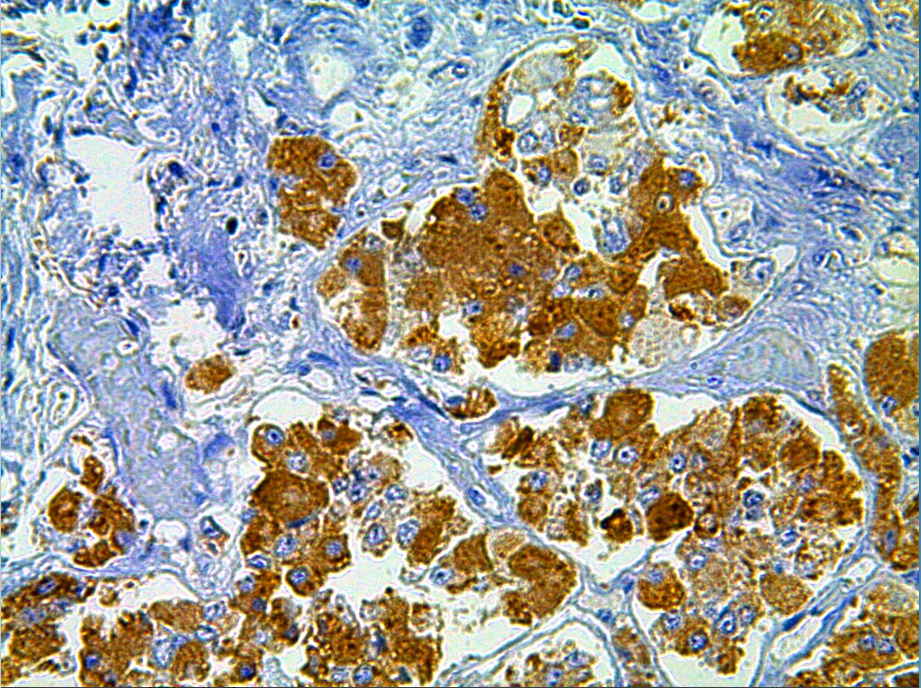

Cellular localization: cytoplasm

Positive control: Pituitary gland

Follicle-stimulating hormone is a hormone secreted by the pituitary gland. In women, it promotes the development and maturation of follicles; in men, it promotes sperm production. This antibody reacts with human FSH and is mainly used in research on the functional classification of pituitary adenomas.

FSH antibody reagents can specifically bind to FSH molecular antigens. Immunohistochemistry kits containing FSH antibody reagents are suitable for the auxiliary diagnosis of autoimmune hypophysitis or reproductive endocrine disorders.